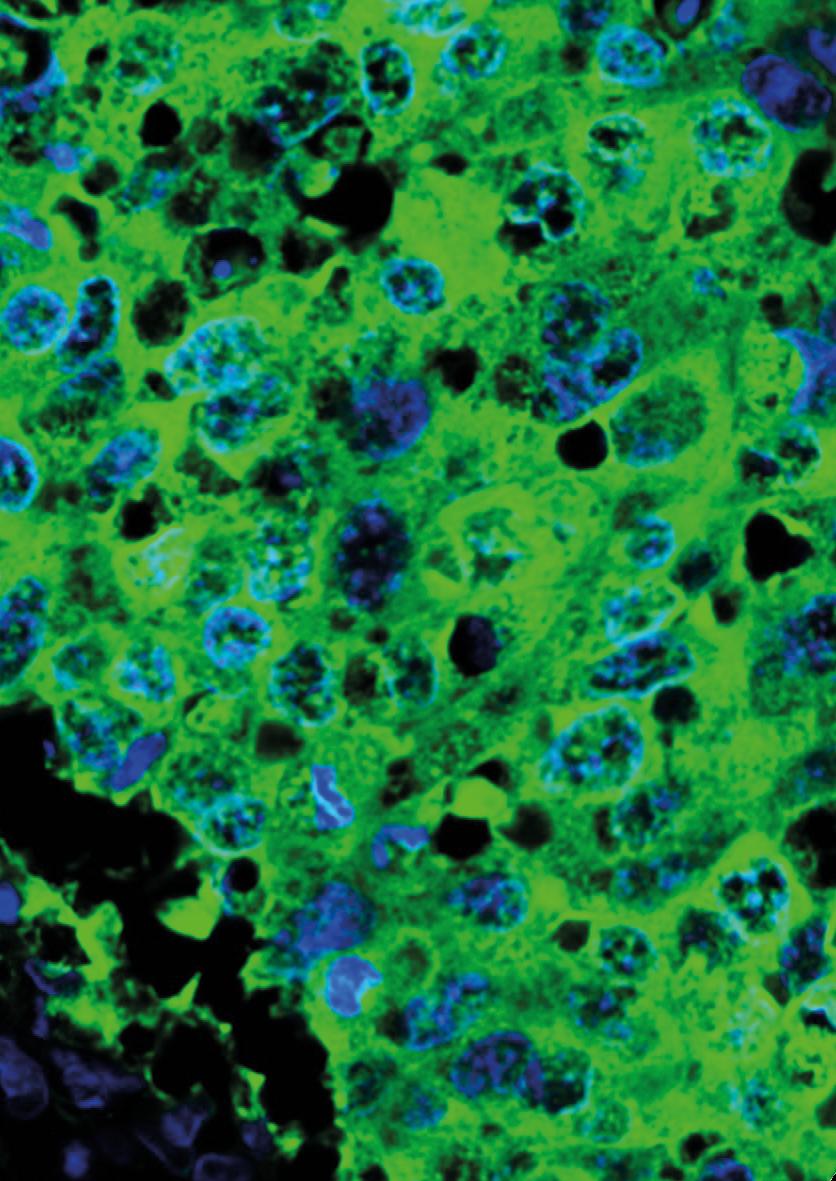

Basal-like breast cancer is an aggressive type of the disease. It often affects younger people and is more common among those from African or South Asian backgrounds – a core part of East London’s population. This type of cancer grows quickly and is hard to treat with traditional methods like chemotherapy.

With the support of Barts Charity funding, Professor Cleo Bishop, based at the Blizard Institute, has been leading a research project along with the Drug Discovery Unit at the University of Dundee, that is developing a new treatment. Called the “one-two punch”, it aims to halt tumour cell growth and can potentially make cancer cells visible to the immune system and easier to attack. This method could be a more targeted and effective treatment with fewer side effects, offering a better prognosis for patients.

“One-two punch” therapy

1. First punch: Stop the growth

Using chemical compounds, tumour cells are forced into a “pro-senescence” state –similar to a sleep-like state in which they can no longer divide or grow. This makes the cancer cells sensitive to the next stage.

2. Second punch: Kill the cancer cells

Once the cancer cells have stopped growing, the second step is to use drugs to kill them. It’s like delivering a knockout punch to the cancer cells after they’ve been immobilised.

The team is now working with the Drug Discovery Unit at the University of Dundee and ValiRx, a drug development company, to advance the new treatment and license it. This could have enormous benefits for patients soon.